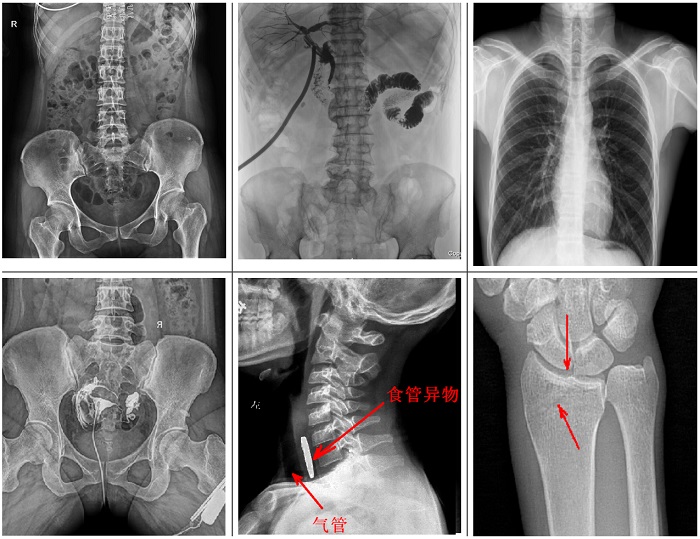

不同于傳統(tǒng)靜態(tài)懸吊DR,普利德多功能懸吊動(dòng)態(tài)DR搭載動(dòng)態(tài)平板探測(cè)器,同時(shí)具備數(shù)字?jǐn)z影、透視、造影功能,全脊柱、全下肢圖像拼接等功能,臨床應(yīng)用更加廣泛,可通過動(dòng)態(tài)實(shí)時(shí)連續(xù)成像,對(duì)于重疊部位病灶或者易被遮擋的病灶進(jìn)行多角度動(dòng)態(tài)觀察,極大的提升篩查診斷的精準(zhǔn)性。

可供各級(jí)醫(yī)院進(jìn)行人體頭部、頸部、胸部、腹部、腰椎、四肢等部位的臥位、正位、側(cè)位、斜位的數(shù)字化攝影、透視及造影檢查;適用于各級(jí)醫(yī)院臨床各個(gè)科室,滿足放射科、體檢中心、影像中心、內(nèi)科、外科 、急診科、骨科、創(chuàng)傷科、消化科等科室的多種臨床檢查需求。